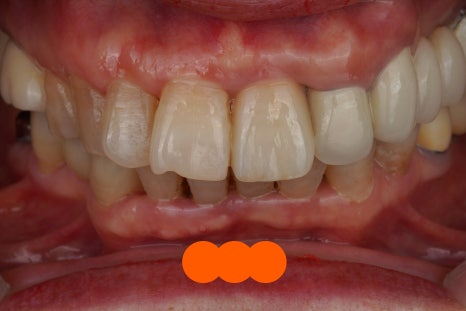

아래 앞니 신경치료 및 크라운 케이스

위 앞니 발치 즉시 임플란트, 크라운 케이스